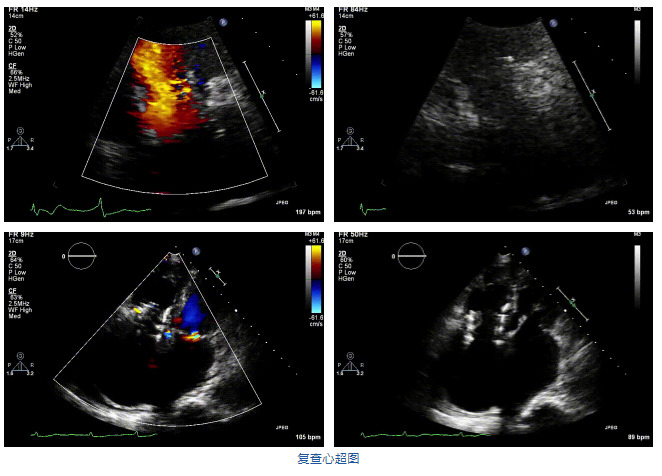

2021年12月7日,復(fù)旦大學(xué)附屬中山醫(yī)院葛均波院士團隊完成的首批兩例LuX-Valve Plus經(jīng)血管三尖瓣置換患者順利出院,從患者入院至出院僅歷時一周時間,出院時患者狀態(tài)恢復(fù)良好,復(fù)查心超三尖瓣無反流。

結(jié)合術(shù)前CT評估結(jié)果,葛均波院士團隊最終決定選用LuX-Valve Plus 50mm和55mm兩種型號的瓣膜,并于2021年11月30日順利完成LuX-Valve Plus經(jīng)血管三尖瓣置換術(shù),手術(shù)室即刻拔除氣管插管,術(shù)后第二天轉(zhuǎn)出心內(nèi)科監(jiān)護室,下床活動。術(shù)后患者三尖瓣反流癥狀得到顯著改善,復(fù)查心超結(jié)果顯示人工三尖瓣瓣膜支架固定穩(wěn)定,瓣葉關(guān)閉形態(tài)未見異常,未見明顯反流。

在本次救治性臨床研究中,治療的兩例患者病因不同,解剖結(jié)構(gòu)復(fù)雜,均為極重度三尖瓣反流,手術(shù)最終都順利植入了LuX-Valve Plus三尖瓣人工瓣膜。術(shù)后超聲顯示瓣膜支架固定穩(wěn)定,反流癥狀顯著改善,取得了良好臨床治療效果。